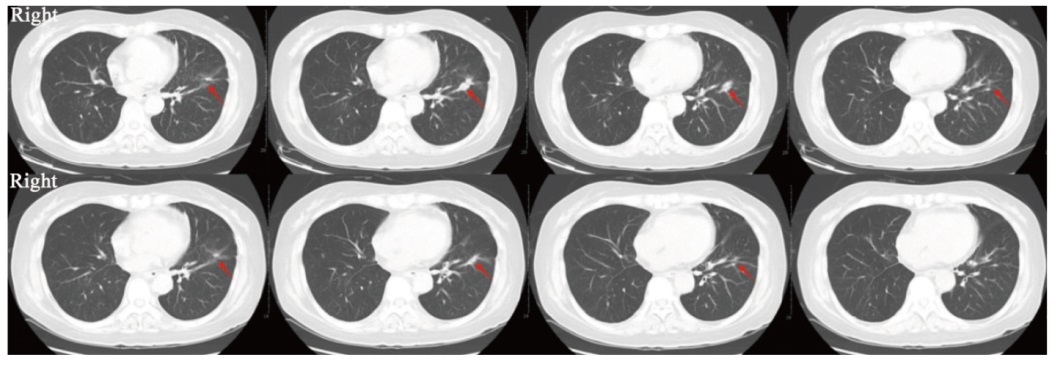

| 图4 第5例患者治疗前后肺部原发灶对比 |

| Fig. 4 Comparison of primary lung lesions before and after treatment in the fifth patient The red arrow indicates the regressed primary lung lesion. |